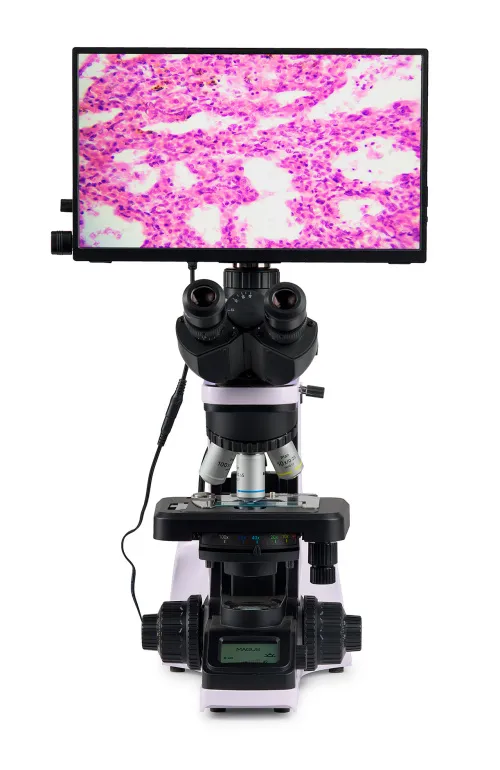

MAGUS Bio D240T LCD Biological Digital Microscope

With a camera and a monitor. Magnification: 40–1000x. Trinocular microscope head, coded revolving nosepiece, plan achromatic objectives, 3W LED illuminator, and intelligent lighting control system

The microscope is suitable for observing transparent and translucent biological samples, such as smears and cross sections using the brightfield microscopy technique in transmitted light. The coded revolving nosepiece maintains a comfortable brightness level when the objectives are changed. The microscope's intelligent lighting control system improves comfort and speed of the researcher’s everyday work. Smart features help students ease into the profession and gain the professional experience they need. Practical aspects play an important role for student microscopes. The size, weight, ease of storage of the cords, and the microscopes themselves are important in everyday use. This microscope is convenient to move around on a table due to its small dimensions and low weight. It does not take up much space in storage. It is equipped with a 2MP camera with an HDMI interface. The digital camera outputs the image directly on the monitor screen with no connection to a computer. The software complements the system with analysis and documentation functions. The monitor in the digital microscope has Full HD resolution.

Monitor

The MAGUS MCD20 Monitor is designed to use a visualization system of the MAGUS microscope. It is connected to a camera mounted on the microscope to display real-time images. It is compatible with MAGUS HDMI cameras operating in Full HD resolution. The screen diagonal is 13.3 inches. The IPS sensor delivers a bright image with large viewing angles: If you look at the monitor at an angle, there is no color distortion. The display can be placed on a folding stand on a table or mounted directly on the camera, whichever is more convenient for the user.